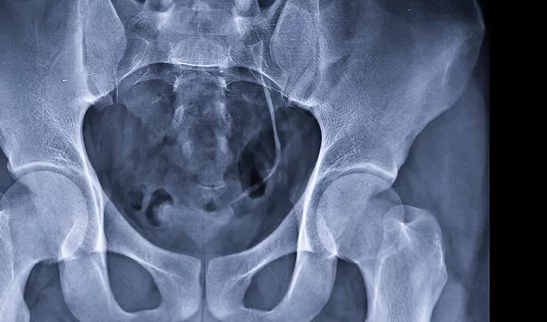

• Des examens complémentaires peuvent être prescrits (échographie, scanner, IRM, bilan sanguin ou urinaire)

En fonction de votre situation, certains examens sont effectués sur place dans notre établissement :

• Imagerie médicale

• Biopsies ciblées si une anomalie est suspectée (notamment de la prostate, avec technologie de fusion si nécessaire)